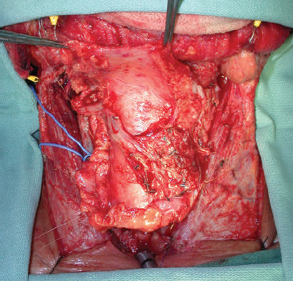

CHAPTER The oral cavity consists of the following structures: the lips, buccal mucosa, mandibular and maxillary alveolar ridge, retromolar trigone, hard palate, floor of the mouth, and anterior (oral or mobile) tongue. The pharynx is anatomically divided into the oropharynx, nasopharynx, and hypopharynx. The oropharynx is bounded by the nasopharynx superiorly, the oral cavity anteriorly, and the hypopharynx and larynx inferiorly. The main structures in the oropharynx are the base of tongue, tonsillar pillars, lateral and posterior oropharyngeal walls, and soft palate. The hypopharynx extends from the level of the hyoid bone to the lower border of the cricoid cartilage, which is congruous with the cervical esophagus below. This is a critical area that is responsible for airway protection and swallowing and speech functions. Common malignancies in the oral and pharyngeal regions include those of the lip, buccal area, floor of mouth, tongue, tonsils, hypopharynx, and larynx. The treatment of these lesions often results in surgical defects that can significantly affect the appearance and function of these vital structures. Providing basic tissue coverage for these defects without considering the functional and aesthetic outcomes is no longer acceptable in modern-day practice. Unfavorable outcomes are common in these complex reconstructions. Proper reconstruction of such defects may prevent life-threatening complications, restore essential functions such as swallowing and speech, and improve patients’ quality of life and self-image. Major head and neck surgery and free flap reconstruction pose significant perioperative risks for patients. Medical complications, not surgical complications, have been proven responsible for slow recovery, prolonged hospital stay, and poor outcomes.1 A thorough medical evaluation and consultation to the medical services before surgery are often required. Many head and neck cancer patients have a long history of tobacco and alcohol abuse. Pulmonary function should be evaluated in those with chronic obstructive pulmonary disease, and cardiovascular workup should be performed as indicated. Preoperative optimization of heart and lung functions is essential to reduce perioperative mobility and mortality. A history of peripheral vascular disease and carotid artery disease has a great impact on the flap selection, recipient vessel selection, and risks for perioperative cerebrovascular accidents. Carotid artery diseases can also be identified on head and neck CT images, which may demonstrate calcification and stenosis. Vascular specialists should be consulted when significant peripheral vascular diseases and carotid stenosis are present. Diabetes is also prevalent in this patient population and increases the risk of surgical site infection. Proper glucose control is essential. Summary Box Complications After Glossectomy and Pharyngoesophageal Reconstruction Choice of flaps is extremely important for oral and pharyngeal reconstruction. Specific defects require several considerations: • Specific flaps with appropriate thickness • Pedicle length • Ability to carry both skin and muscle • Possibility of two skin islands • Skin color match • Donor site morbidity The thickness of the flap affects not only postoperative function, but aesthetic outcomes as well. The paucity of recipient vessels may demand a flap with a long vascular pedicle to obviate vein grafting in an already-complex setting. Therefore, depending on the defects, surgical goals, and availability of recipient vessels, the choice of flap should be carefully evaluated in the preoperative planning session. The patient and family should be made fully aware of potential functional deficits, including the possibility of long-term tube feeding and tracheostomy dependency. Common donor sites such as the forearm, anterolateral thigh (ALT), abdomen, and anterior chest should be evaluated for skin quality and thickness, history of surgery or trauma, and vascular disease. Hand dominance should also be documented. A bracelet with the words “NO IV” is placed on the potential donor site arm, typically the one with the nondominant hand. Defects in the floor of mouth may vary from a small mucosal defect to a large defect involving the musculature with exposed bone. The latter often require postoperative radiotherapy, which significantly influences the methods of reconstruction. Isolated floor-of-mouth defects that do not include the suprahyoid musculature may be skin grafted or reconstructed with a facial artery musculomucosal (FAMM) flap.2,3 However, ligating and dividing the facial artery is common practice during a neck dissection. Therefore reconstruction using the FAMM flap may not be possible for patients who have had a neck dissection. When the floor-of-mouth defect extends to the upper neck, with resection of part of the suprahyoid musculature and exposure of the mandible, more extensive flap reconstruction is indicated. In high-risk patients, the pectoralis major flap is a viable option to fill the dead space in the floor of the mouth and upper neck. In young and more functional patients, however, a free flap is preferred to minimize neck deformity and maximize function. Fig. 51.1 A forearm flap can provide a thin and pliable skin for floor-of-mouth reconstruction that allows full mobility of the tongue. Fig. 51.2 When there is a large soft tissue defect in the floor of mouth, an anterolateral thigh flap with a segment of vastus lateralis muscle can provide reliable coverage and dead space filling. Fig. 51.3 (a) A bulky flap in the floor of mouth can interfere with tongue and lip function. (b) Flap thinning is possible with suction-assisted lipectomy and direct excision at the end of debulking. (c) One year later. The common problems after this type of reconstruction may include a bulky flap that limits tongue mobility and function or inadequate filling of dead space causing infection, fistula, and subsequent bone exposure that may delay adjuvant therapy and cause osteoradionecrosis. The goals are to effectively obliterate the dead space and protect the mandible from postoperative radiotherapy without unwanted bulk that may impede tongue mobility and oral function. A radial forearm flap or ulnar artery perforator (UAP) flap is ideal because they provide a thin and supple lining (Fig. 51.1). A thin ALT flap can also be used to reconstruct the floor of the mouth, with a segment of the vastus lateralis muscle used to fill the dead space (Fig. 51.2). This flap is particularly useful for large defects involving the entire suprahyoid musculature, especially after previous radiation. A shallow floor-of-mouth defect should not be covered with a bulky flap, because it may restrict tongue mobility and obliterate the lingual sulcus, causing drooling (Fig. 51.3). When the resection involves the mandibular gingiva and labial mucosa up to the vermilion border, a common mistake is to suture the flap all the way to the vermilion. This will push the lip downward and completely obliterate the labial sulcus, causing drooling, oral incompetence, and inability to eat and drink. Therefore the flap edge should be sutured to the labial tissue at the base of the labial sulcus. The remaining labial mucosal defect can be left to remucosalize or can be skin grafted. The remucosalization process takes approximately 1 week. The same principle applies to mandibular reconstruction with a fibular osteocutaneous flap when the labial mucosa defect extends to the vermilion (Fig. 51.4). Floor-of-mouth defects commonly involve the ventral tongue. A common practice is to close the tongue to itself by folding the lateral edges of the tongue ventrally and to reconstruct the floor of the mouth with a flap. This technique creates a small “snake tongue” (see Fig. 51.3a) that often causes impairment of speech and swallowing functions. A better approach is to resurface the ventral tongue and the floor of the mouth simultaneously with a thin forearm flap (Fig. 51.5) to preserve the bulk and mobility of the tongue. The tongue is a highly functional organ. A common problem after partial tongue reconstruction is the tethering of the remaining tongue, limiting tongue mobility and function. The most important goal for partial or hemiglossectomy reconstruction is, therefore, to preserve the remaining tongue function. Small defects of up to one quarter or even one third of the tongue, with minimal resection of the floor of the mouth and no communication to the neck, may be closed primarily or with a skin graft (Fig. 51.6). Resection of the floor of the mouth combined with a neck dissection creates a connection between the oral cavity and the neck along the lingual cortex of the mandible. These defects are best reconstructed with a flap to eliminate the dead space, minimizing the risk of infection and fistula formation. The remaining tongue has the ability to move intelligibly as long as it is not tethered. A bulky flap will push the remaining tongue to the side and obstruct its mobility. Therefore a thin and pliable flap should be chosen. The radial forearm flap or UAP flap is usually the first choice. Some adipose tissue in the upper forearm may be included to obliterate the submandibular dead space (Fig. 51.7). A thin ALT flap with a strip of the vastus lateralis muscle can be a good option as well. Fig. 51.4 (a) When resection of labial mucosa approaches the vermilion border, suturing the flap to the mucosal margin may obliterate the labial sulcus and push the lower lip down, causing drooling. (b) A better approach is to inset the flap to the bottom of the labial sulcus and leave the raw surface on the lip to remucosalize. This will preserve the labial sulcus and prevent drooling. Fig. 51.5 (a) After resection of the ventral tongue, closure of the remaining mobile tongue to itself may result in a “snake tongue,” with significant volume loss. (b) An alternative approach to reconstructing the ventral tongue defect is to use a thin forearm flap, part of which is also used to reconstruct the floor of the mouth. To avoid tethering of the remaining tongue, careful flap insetting is important. The length of the ventral tongue, defined as the distance from the tip of tongue to its junction with the floor of mouth and gingiva, is approximately 5 to 6 cm. The distal end of the flap is oriented toward the tip of the remaining tongue. The distal flap width, usually 6 cm, matches the ventral tongue length (Fig. 51.8). Thus one corner of the distal flap is sutured to the tip of tongue, and the other corner to the gingiva. The rest of the flap is sutured to the dorsal tongue medially and gingiva laterally. Such insetting re-creates a nice ventral sulcus and lateral gutter (Fig. 51.9). When there is no gingiva left to attach the flap to, it can be sewn to the teeth by tying the suture knots around the teeth. A single layer of interrupted 3–0 Vicryl sutures usually suffices, although some surgeons prefer horizontal mattress sutures. It is important, however, not to tie the horizontal mattress sutures too tight, which may lead to flap–mucosa edge necrosis and fistula formation. Fig. 51.6 For partial tongue defects without bone exposure or communication to the neck, full-thickness skin grafts can provide excellent coverage with preservation of tongue mobility. Fig. 51.7 (a) Partial glossectomy with neck dissection often leaves a submandibular or upper neck dead space. A conventional radial forearm flap may not have extra tissue to obliterate the dead space. (b,c) A portion of the adipofascial tissue from the upper forearm based on a proximal perforator can be included in the radial forearm for this purpose. Fig. 51.8 For hemiglossectomy reconstruction, the goal is to preserve the remaining tongue mobility without tethering. Adequate ventral sulcus and lateral gutter should be re-created with a 6 to 7 cm wide flap. The distal width of the radial forearm flap is used to re-create the ventral sulcus of the mobile tongue to prevent tethering. Fig. 51.9 With proper flap insetting, the ventral sulcus and lateral gutter of the tongue can be re-created to achieve tongue mobility. Sensory reinnervation can improve swallowing function and patient satisfaction. This can be achieved by coapting the sensory nerve of the flap to the divided lingual nerve. Sensory recovery of the flap with this technique has been well documented. The radial forearm flap, UAP flap, ALT flap, and lateral arm flap can all potentially provide sensory reinnervation.4–9 Unlike hemiglossectomy, a total or subtotal glossectomy leaves no meaningful tongue muscle. Functional outcomes are poor, and aspiration can be a serious complication necessitating a total laryngectomy in some patients. Common problems after total and subtotal glossectomy reconstruction include inadequate bulk resulting in a “funnel tongue,” inadequate vascularized tissue filling resulting in infection and fistula formation, and risks of aspiration related to resection of all floor-of-mouth musculature (Fig. 51.10). The goal of reconstruction is to create enough bulk for the neotongue. Tissue bulk is important for reconstructing large defects of the tongue for two reasons. First, it is needed to help the neotongue touch the palate to produce better speech and push food toward the hypopharynx. Second, the tissue bulk diverts saliva and food to the lateral gutters during swallowing to minimize aspiration.10 With these goals, a bulky flap should be chosen. Some muscle is also needed to obliterate the dead space in the floor of mouth and upper neck. This makes the ALT flap the ideal choice. It also has the advantages of providing sensory and motor reinnervation (Fig. 51.11). The rectus abdominis myocutaneous (RAM) is another good option. Obese men often have more adipose tissue in the abdomen than in the thighs. The opposite may be true for women. It has been suggested by some surgeons to remove the thick cutaneous portion of the flap and use the muscle only. Muscle flaps with or without skin grafts are, however, prone to atrophy and will lose significant bulk, especially after radiotherapy, resulting in a funnel shape that allows food to pour into the hypopharynx and larynx, causing aspiration. A forearm flap is usually too thin for total or subtotal glossectomy defects. Fig. 51.10 A total glossectomy with resection of all floor-of-mouth musculature leaves no tongue muscle to function and increases the risk of aspiration because of the drop of the larynx. Fig. 51.11 Both sensory and motor reinnervation is possible with the anterolateral thigh flap with a segment of the vastus lateralis muscle for total glossectomy reconstruction. (a) The lingua nerve is used for sensory reinnervation. (b) The hypoglossal nerve is used for motor reinnervation. During flap insetting, a dome of neotongue is created so that it can touch the palate easily (Fig. 51.12). Flap insetting can be difficult in a narrow jaw, particularly when no mandibular gingiva is left. It is helpful to inset the flap before revascularization while the flap is still “empty.” In addition to a funnel tongue, drop of the larynx can cause aspiration, which often occurs during a total glossectomy because the suprahyoid musculature is removed. The risk can be reduced with laryngeal suspension. Laryngeal suspension is often performed with circumhyoid sutures (0–0 Prolene) placed through drill holes in the mentum on both sides of the midline.11 The distance between the hyoid bone and the mentum is approximately 4.5 to 5 cm (Fig. 51.13). Care should be taken to avoid compression of the vascular pedicle by these suspension sutures. Fig. 51.12 Volume is necessary for total glossectomy reconstruction to reduce the risk of aspiration and improve swallowing and speech functions. Functional muscle transfer has been successfully used to restore upper extremity functions and for facial reanimation. However, it is rarely used in tongue reconstruction and produces uncertain results. My experience and that of others12,13 have shown minimal muscle movements after a functional muscle flap such as a gracilis flap or ALT flap with the vastus lateralis muscle by coapting the motor nerve of the flap to the hypoglossal nerve. My current approach is to use the ALT flap with vastus lateralis muscle with both sensory and motor reinnervation, because these additional procedures are easy to perform and add little extra time. Without postoperative radiotherapy, reinnervation of the muscle may prevent muscle atrophy. Postoperative radiotherapy, however, may destroy the motor end plates before reinnervation occurs. As with partial glossectomy reconstruction, sensory reinnervation may improve swallowing functions and patient satisfaction.8 Fig. 51.13 After a total glossectomy, static laryngeal elevation can be achieved with circumhyoid sutures to suspend the larynx to the mandible. The difficulties of postlaryngopharyngectomy reconstruction are mainly the results of previous radiotherapy and neck surgery. This increases the risk for delayed wound healing, fistula formation, infection, carotid artery rupture, lack of recipient vessels, a combined pharyngoesophageal and neck skin defect, and tracheoesophageal puncture (TEP) complications. Functional outcomes such as speech and swallowing can be disappointing as well. In addition to being nonvocal after a total laryngopharyngectomy, postreconstruction complications such as pharyngocutaneous fistulas and anastomotic strictures may render patients dependent on tube feeding. Radiotherapy has become the primary treatment for early stages of squamous cell carcinoma in the larynx and hypopharynx. Therefore the majority of laryngopharyngectomy cases are recurrent cancers that have failed radiotherapy and, in some cases, previous neck dissection. These defects are among the most difficult to repair in head and neck reconstruction. The reconstructive goals are to provide alimentary tract continuity, protect great vessels, maximize TEP speech and swallowing functions, reduce the risk of fistula formation, and minimize neck deformity and donor site morbidity. The choice of flaps for pharyngoesophageal reconstruction is important. The flap has a great impact on defect coverage, restoration of speech and swallowing functions, simultaneous neck resurfacing and tracheostoma reconstruction, and donor site morbidity. Commonly used flaps include the ALT flap, jejunal flap, radial forearm flap, and pectoralis major myocutaneous flap.14–20 The pectoralis flap gained popularity in the early 1980s but is used less now because of advances in free flap reconstruction. In general, enteric flaps heal fast but tracheoesophageal (TE) speech is poor and donor site morbidity is higher. Conversely, fasciocutaneous flaps heal slower but TE speech is superior and donor site morbidity is minor.21,22 ALT flaps have largely replaced jejunal and radial forearm flaps in the last decade. If the ALT flap is unavailable because of a lack of perforators or is deemed too bulky, a radial forearm flap or ulnar artery perforator flap is the next choice. In otherwise healthy patients with a circumferential defect, the jejunal flap is another good choice. Contraindications of the jejunal flap include significant comorbid diseases, obesity, and a history of abdominal or gastrointestinal surgeries. The pectoralis major flap can be used for partial defects in male patients, for salvage after failed free flap reconstruction, or in very high-risk patients who cannot tolerate a free flap surgery. The advantage of ALT flaps over forearm flaps is that an ample amount of fascia, the vastus lateralis muscle, and a large second skin paddle can be included for better coverage of the soft tissue defect in the neck, thus potentially reducing the risk of fistula formation. The flap is usually partially inset before revascularization. Recipient vessel choices include the branches of the external carotid artery and facial vein. In a previously radiated and operated neck, using the transverse cervical vessels may avoid difficult and risky dissection around the carotid artery.23,24 Before closure of the neck incision, the neck is slightly flexed with the head in a neutral position. This repositioning may cause kinking or twisting of the vascular pedicle. Therefore the vascular pedicle should be carefully inspected again before closing the neck incision. The second skin paddle is then turned outward to resurface the neck, to reconstruct the tracheal defect, or for flap monitoring. To monitor a buried flap without an external skin island, I prefer externalizing a small skin island based on a second cutaneous perforator or externalizing a small amount of the vastus lateralis muscle based on a muscular branch.25 This technique is highly reliable, because three-dimensional assessment of the entire skin or muscle is possible. This second skin island or muscle is then brought out through the neck incision and covered with petroleum jelly–impregnated gauze to prevent desiccation. A 2–0 silk tie may be placed around the perforator at the skin level so that the pedicle can be easily tied when it is time to remove the monitor segment. The monitor is removed 5 to 7 days later, before the patient is discharged from the hospital. Alternatively, a handheld Doppler device can be used to monitor the perforator or the main vascular pedicle through the neck skin. The Flow Coupler (Synovis) provides an additional method of flap monitoring. With the jejunal flap, a 3 to 4 cm long monitor segment is created from the remaining jejunum based on branches of the pedicle vessels. Both ends of the bowel segment are left open to avoid distention. At the time of neck closure, the tracheostoma is sutured to the surrounding neck and anterior chest skin, and a No. 8 Shiley tracheostomy tube is placed in the tracheostoma and secured to the chest skin. Fig. 51.14 During flap insetting for circumferential pharyngoesophageal reconstruction, positioning the perforators of the anterolateral thigh flap posteriorly may cause perforator compression against the vertebrae and flap failure. Fig. 51.15 The longitudinal seam of the tubed anterolateral thigh flap is positioned more posteriorly with the perforators in the anterior location to avoid compression and kinking. When the ALT flap is tubed to reconstruct a circumferential defect, the perforators need to be carefully positioned. If they are positioned posteriorly against the prevertebral fascia, the swelling of the flap can easily compress the perforators against the hard surface of the vertebrae, causing flap failure (Fig. 51.14). During flap insetting, the proximal anastomosis between the flap and the base of tongue is usually performed first. The longitudinal seam is positioned posterolaterally at the 4 or 8 o’clock position for easy suturing of the T junction. It can be positioned at 6 o’clock if the flap is tubed first. Anastomosis starts with two corner sutures at the 3 and 9 o’clock positions. The posterior wall is then completed, followed by the anterior wall. The tubed flap is slightly twisted so that the longitudinal seam at the distal anastomosis is facing posteriorly at the 6 o’clock position. Such positioning of the tubed flap places the perforator vessels anteriorly between the 11 and 1 o’clock positions to avoid compression of the perforators against the prevertebral fascia. The entire vascular pedicle can be placed anteriorly across the flap to avoid sharp kinking (Fig. 51.15). Anastomotic strictures can result from a circular scar formation, inadequate diameter, a thick flap, postoperative radiation, or fistula. To obtain a sufficient lumen, a flap width of 9.4 cm is required to achieve a 3 cm diameter (3π) for the tubed neopharynx or esophagus.19 For partial defects, the width of the flap is calculated by subtracting the width of the remaining pharyngeal mucosa from 9.4 cm. The flap can be thinned as needed by direct excision of subcutaneous fat at the periphery of the flap. Ample subcutaneous tissue should be left around the cutaneous perforators, and 2 to 3 mm of subcutaneous tissue is left on the dermis to protect the subdermal plexus. The anterior wall of the cervical esophagus is split longitudinally for approximately 1.5 cm to spatulate the distal anastomosis (Fig. 51.16). This is important to enlarge the distal anastomosis and minimize the risk of ring stricture. On the flap side, a triangular lip is created and inserted into the longitudinal split of the esophagus to complete the spatulation (Fig. 51.17). A Montgomery salivary bypass tube with a diameter of 14 mm can be placed inside the tubed flap during circumferential reconstruction in some patients. This technique may further reduce stricture and fistula formation. The indications for the use of the Montgomery tube include a thick flap, difficult flap insetting, very low location of the transected cervical esophageal end, small cervical esophagus, or poor tissue quality because of radiation injury. The tube is inserted through the mouth before the longitudinal seam of the flap is completed. The proximal flange of the bypass tube is placed above the proximal anastomosis, and the distal end is placed in the esophagus below the distal anastomosis. A 1–0 Prolene suture is attached to the flange of the tube, brought out through the mouth, and taped to the cheek to prevent distal migration and facilitate easy removal of the tube. A 10 Fr red rubber catheter is placed over the Prolene suture to protect the oral commissure (Fig. 51.18). Fig. 51.16 To spatulate the distal anastomosis to minimize ring strictures, the anterior cervical esophagus is incised longitudinally for approximately 1.5 cm. Fig. 51.17 A triangular lip of flap is created to be inset to the longitudinal opening of the cervical esophagus to complete the spatulation. Fig. 51.18 For some patients, a Montgomery salivary bypass tube can be placed in the reconstructed esophagus to minimize the risks of leakage and stenosis. (a) A Prolene suture is placed on the flange of the tube and taped to the cheek. (b) A small red rubber catheter is placed over the Prolene suture to prevent the suture cutting through the oral commissure. If a feeding tube has not yet been placed, a Dobbhoff feeding tube is placed through the nose and flap or inside the Montgomery salivary bypass tube, and through the cervical esophagus to the stomach. The Montgomery tube is usually removed 4 to 6 weeks after reconstruction. This can be done in the clinic without sedation by pulling out the previously placed Prolene suture. In my experience, pharyngocutaneous fistulas occur in 6% of patients.19,20 Fistula rates are similar in partial and circumferential reconstructions. Pharyngocutaneous fistulas occur more commonly at the distal anastomosis than at the proximal anastomosis, most likely related to the thin, less well-vascularized cervical esophagus compared with the base of the tongue. In fact, proximal fistulas are rare with the ALT flap unless there is a dehiscence from poor tissue quality. It has been speculated that the longitudinal seam of a tubed fasciocutaneous flap or two longitudinal suture lines in a partial defect might have contributed to a higher incidence of fistula formation with the radial forearm flap. However, in my experience, the fistula rate with the ALT flap is no higher than with the jejunal flap, and no fistulas have occurred through the longitudinal suture lines. Fistulas usually develop between 1 and 4 weeks postoperatively and manifest as leakage of saliva or liquids or, in some patients, as a neck infection. Therefore any neck infection or abscess that occurs after a pharyngoesophageal reconstruction should raise suspicion for anastomotic leakage. Risk factors for fistula formation include improper suturing techniques, poor tissue quality at the anastomosis site, previous radiotherapy, lack of well-vascularized tissue protection of the anastomosis, and turbulent postoperative course. At the time of surgery, any questionable tissue in the proximal pharynx and cervical esophagus should be trimmed until well-vascularized tissue is seen. Although a watertight seal using a horizontal mattress suturing technique is advocated by some, I believe that such tight horizontal mattress suturing may actually cause necrosis of the mucosal edges and thus increase the risk for fistula. I prefer single-layer, simple interrupted 3–0 Vicryl sutures for flap insetting, taking relatively big bites, inverting the skin and mucosal edges into the lumen, spacing each suture 5 to 7 mm apart, and avoiding tight knots. To further protect the suture lines, a second layer of fascial closure is recommended. Fig. 51.19 A novice mistake is to deepithelialize a strip of skin and externalize a portion of the flap for neck coverage. This results in a high fistula rate. Once a leakage occurred in this patient, the de-epithelialized portion reepithelialized quickly because of the lack of contact inhibition, resulting in a nonhealing fistula. During ALT flap harvesting, a wider amount of fascia than skin is included in the flap. When making the anterior incision, the fascial incision is made 1 to 2 cm more medially than the skin incision. Likewise, an additional 1 to 2 cm of fascia is recruited posteriorly. After completion of flap insetting, the extra fascia of the flap is wrapped around the flap to reinforce the suture lines and cover the anastomoses. Placement of the Montgomery salivary bypass tube inside the flap may also reduce the risk of fistula in high-risk patients by protecting the anastomosis from constantly soaking in saliva. If neck resurfacing is needed but only one cutaneous perforator remains, an attempt might be made to externalize a portion of the distal flap by deepithelializing a strip of skin around the distal anastomosis (Fig. 51.19). This, however, results in a high fistula rate.19 Even with a minor leakage, the deepithelialized portion will reepithelialize, causing a nonhealing fistula. The timing for resuming an oral diet after surgery may also have an effect on fistula formation. The radial forearm flap has a reputation of having high fistula rates and having delayed fistulas that occur 4 to 5 weeks after surgery.14,15 A fasciocutaneous flap does not heal as quickly as a jejunal flap once it is immersed in saliva 24 hours a day. This may explain the high incidence of delayed fistula formation. In fact, the anastomosis may experience secondary healing, which could take 4 to 6 weeks. If an oral diet is started early, for instance 7 days after surgery, as with the jejunal flap, fistulas will likely develop with the unhealed fasciocutaneous flap. After fasciocutaneous flap reconstruction, I routinely delay oral intake for 2 weeks in nonirradiated patients and for 4 to 6 weeks in patients who have undergone radiotherapy. Before oral intake, a modified barium swallowing study is performed. If no leaks or fistulas are identified, a liquid diet is started and then advanced to a regular diet as tolerated. In the presence of a leak, oral intake is delayed, and the modified barium swallowing study is repeated in two weeks. Most leaks heal within 2 weeks. In a previously irradiated patient, the tracheostoma is at risk for necrosis and dehiscence. This could be the result of an ischemic tracheostoma itself or ischemic neck and chest skin or tight closure. The blood supply to the trachea arises laterally. Extensive lateral dissection on both sides to skeletonize the trachea should be avoided. When the tracheal stoma is short, excessive undermining of the previously irradiated anterior chest skin to reach a low tracheostoma under tension can easily cause skin necrosis, because it is compressed over the clavicular heads. An alternative approach to mature the anterior wall of the tracheostoma is to use a pedicle internal mammary artery perforator (IMAP) flap.26 Questionable neck skin around the tracheostoma should be débrided, and well-vascularized skin from the flap should be used instead. Full-thickness skin grafting over the vastus lateralis muscle to mature the posterior tracheostoma and anterior neck can provide very stable coverage. Another common problem with the tracheostoma is partial obstruction related to a bulky second skin paddle for external coverage. The skin paddle should be thinned as much as possible at the time of reconstruction. Alternatively, muscle and skin grafting can provide excellent results. When a Shiley tube is placed in the tracheostoma with a bulky skin paddle, the flange of the Shiley tube can cause compression and necrosis of the skin around the tracheostoma. To avoid this, the superior flange of the Shiley tube is trimmed and a longer tube should be used (Fig. 51.20). The flap can also be thinned using suction-assisted lipectomy several months after surgery; this method works extremely well. For tracheoesophageal voice rehabilitation, patients commonly wear a hands-free stoma button. This button needs to sit inside the tracheostoma securely. Ideally, the tracheostoma should have a circumferential flange to secure the voice button without the bowstring of the neighboring sternocleidomastoid (SCM) muscles. This can be achieved by dividing the medial edges of the SCM before neck closure and maturing the tracheostoma using a semivertical mattress suturing technique to create a flange (Fig. 51.21). A frozen or woody neck, defined as severe fibrosis in the neck without tissue planes, is the result of neck surgery (such as neck dissection) combined with radiotherapy.24 Long-standing pharyngocutaneous fistulas usually result in the worst cases of frozen neck. There are three major problems associated with managing a frozen neck during reconstruction: 1. Risk of carotid artery rupture 2. Lack of recipient vessels 3. Concomitant neck skin or tracheal defects